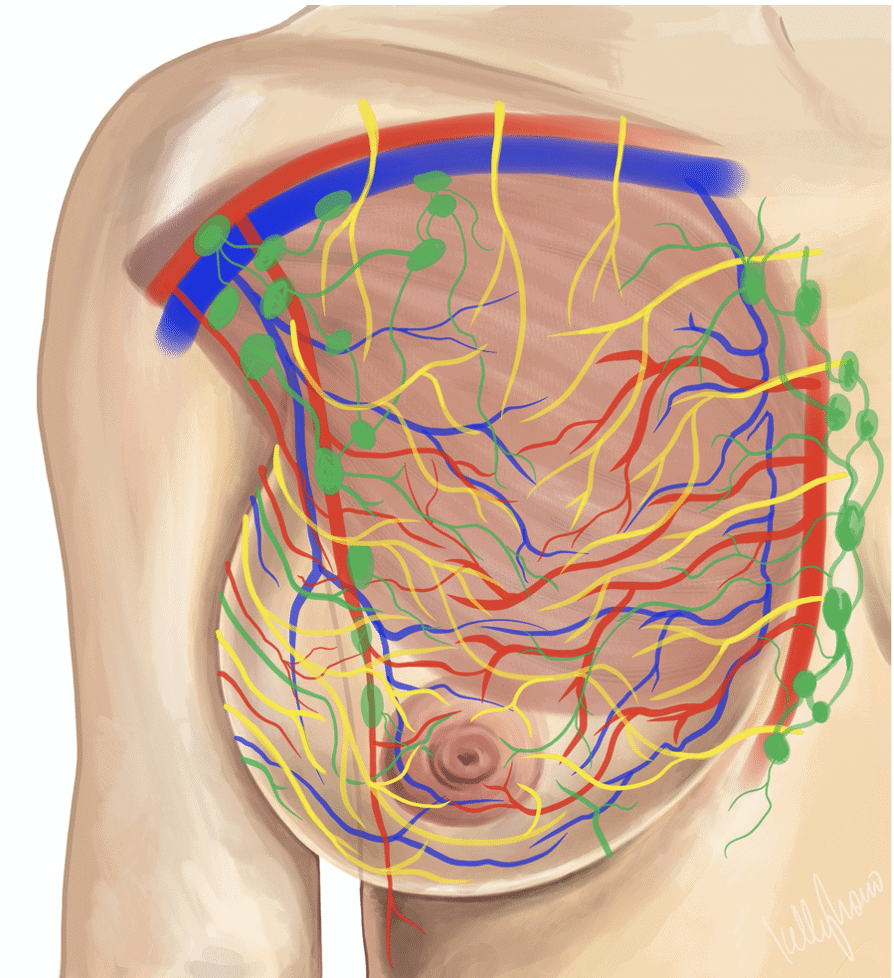

Lactating breasts have incredibly robust blood supply, lymphatic vessels to drain extra fluid, nerves, connective tissue, and functional glandular tissue. There are millions of innumerable, microscopic interlacing ducts in the breast. My hope is that providers and patients can recognize that any forceful physical manipulation of the breast simply causes MORE tissue swelling.